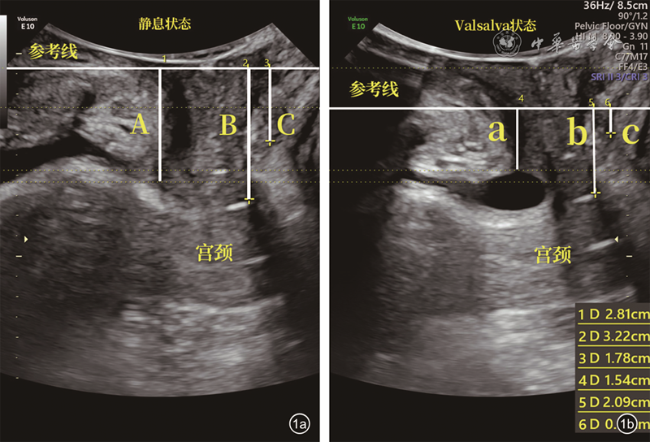

一般临床资料中,PFD组产次及新生儿体质量均值均高于对照组,差异均有统计学意义(P均<0.05),2组年龄及体质量指数比较差异均无统计学意义(P均>0.05);正常对照组和PFD组盆底超声参数BND、PUVA、URA、COD、RAD及LHA比较,差异均有统计学意义(P均<0.05,表1图1, 2, 3)。

图1 正常者静息状态与Valsalva状态超声二维图。图a中A、B、C为静息状态下膀胱颈、子宫颈外口最低点、直肠壶腹部与参考线之间的垂直距离;图b中a、b、c为Valsalva状态下膀胱颈、子宫颈外口最低点、直肠壶腹部与参考线之间的垂直距离(若a、b、c位于参考线下,以负值表示;A-a、B-b、C-c分别为膀胱颈移动度、子宫颈外口移动度以及直肠壶腹部移动度)